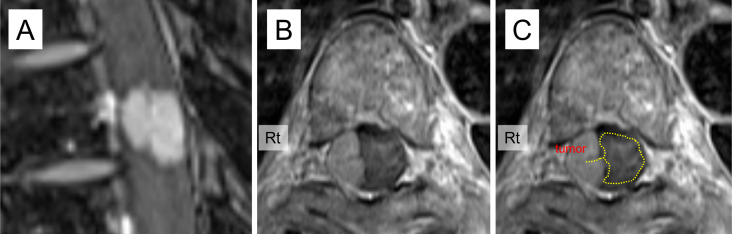

Results: The average age of patients was older (67.6 vs. 58.9 years), and the frequency of females was higher (72% vs. 46%) for meningioma than for schwannoma. Meningiomas were mostly found in the thoracic region (84%), whereas schwannomas were commonly located in the lumbar region (54%). For each tumor type, specific radiological findings were identified. For meningiomas, findings included the ginkgo leaf sign (GLS) (sensitivity 58%, specificity 100%), oval shape (sensitivity 84%, specificity 63%), dural tail sign (DTS) (sensitivity 75%, specificity 100%), and intertumoral calcification (sensitivity 39%, specificity 100%). Combining GLS and DTS greatly improved sensitivity to 89% (specificity 100%). For schwannomas, specific findings included a lobule shape (sensitivity 25%, specificity 95%), dumbbell shape (sensitivity 54%, specificity 100%), and cystic changes (sensitivity 54%, specificity 97%).

Conclusions: GLS may be a specific radiological feature for meningiomas and can aid in diagnosis when combined with DTS. Understanding these distinct radiological characteristics is valuable for preoperative differential diagnosis of intradural-extramedullary spinal tumors.